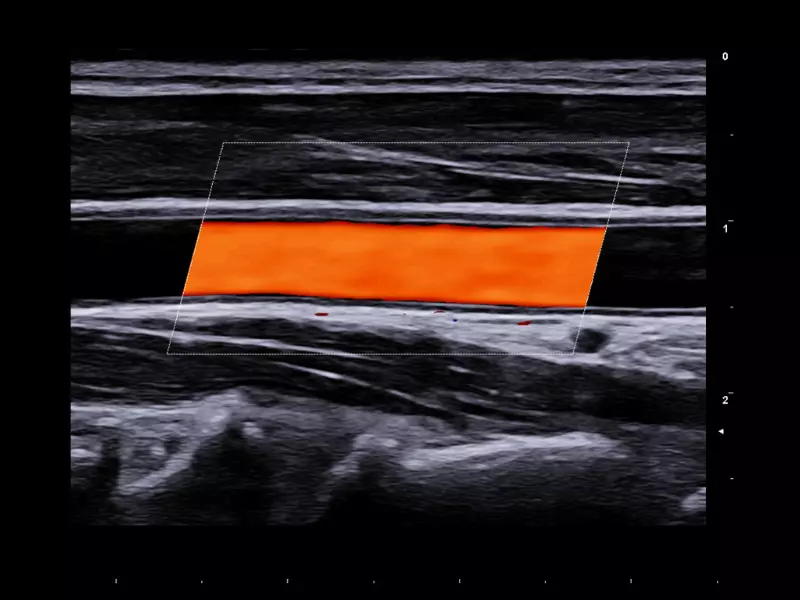

MyLab™9 Platform - QIMT Intima-media thickness quantification based on radio frequencies in real-time studies

MyLab™9 Platform - QIMT Intima-media thickness quantification based on radio frequencies in real-time studies

Q7 - Carotid

Q7 - Carotid

MyLab™X1 - Carotid IMT Calculation

MyLab™X1 - Carotid IMT Calculation